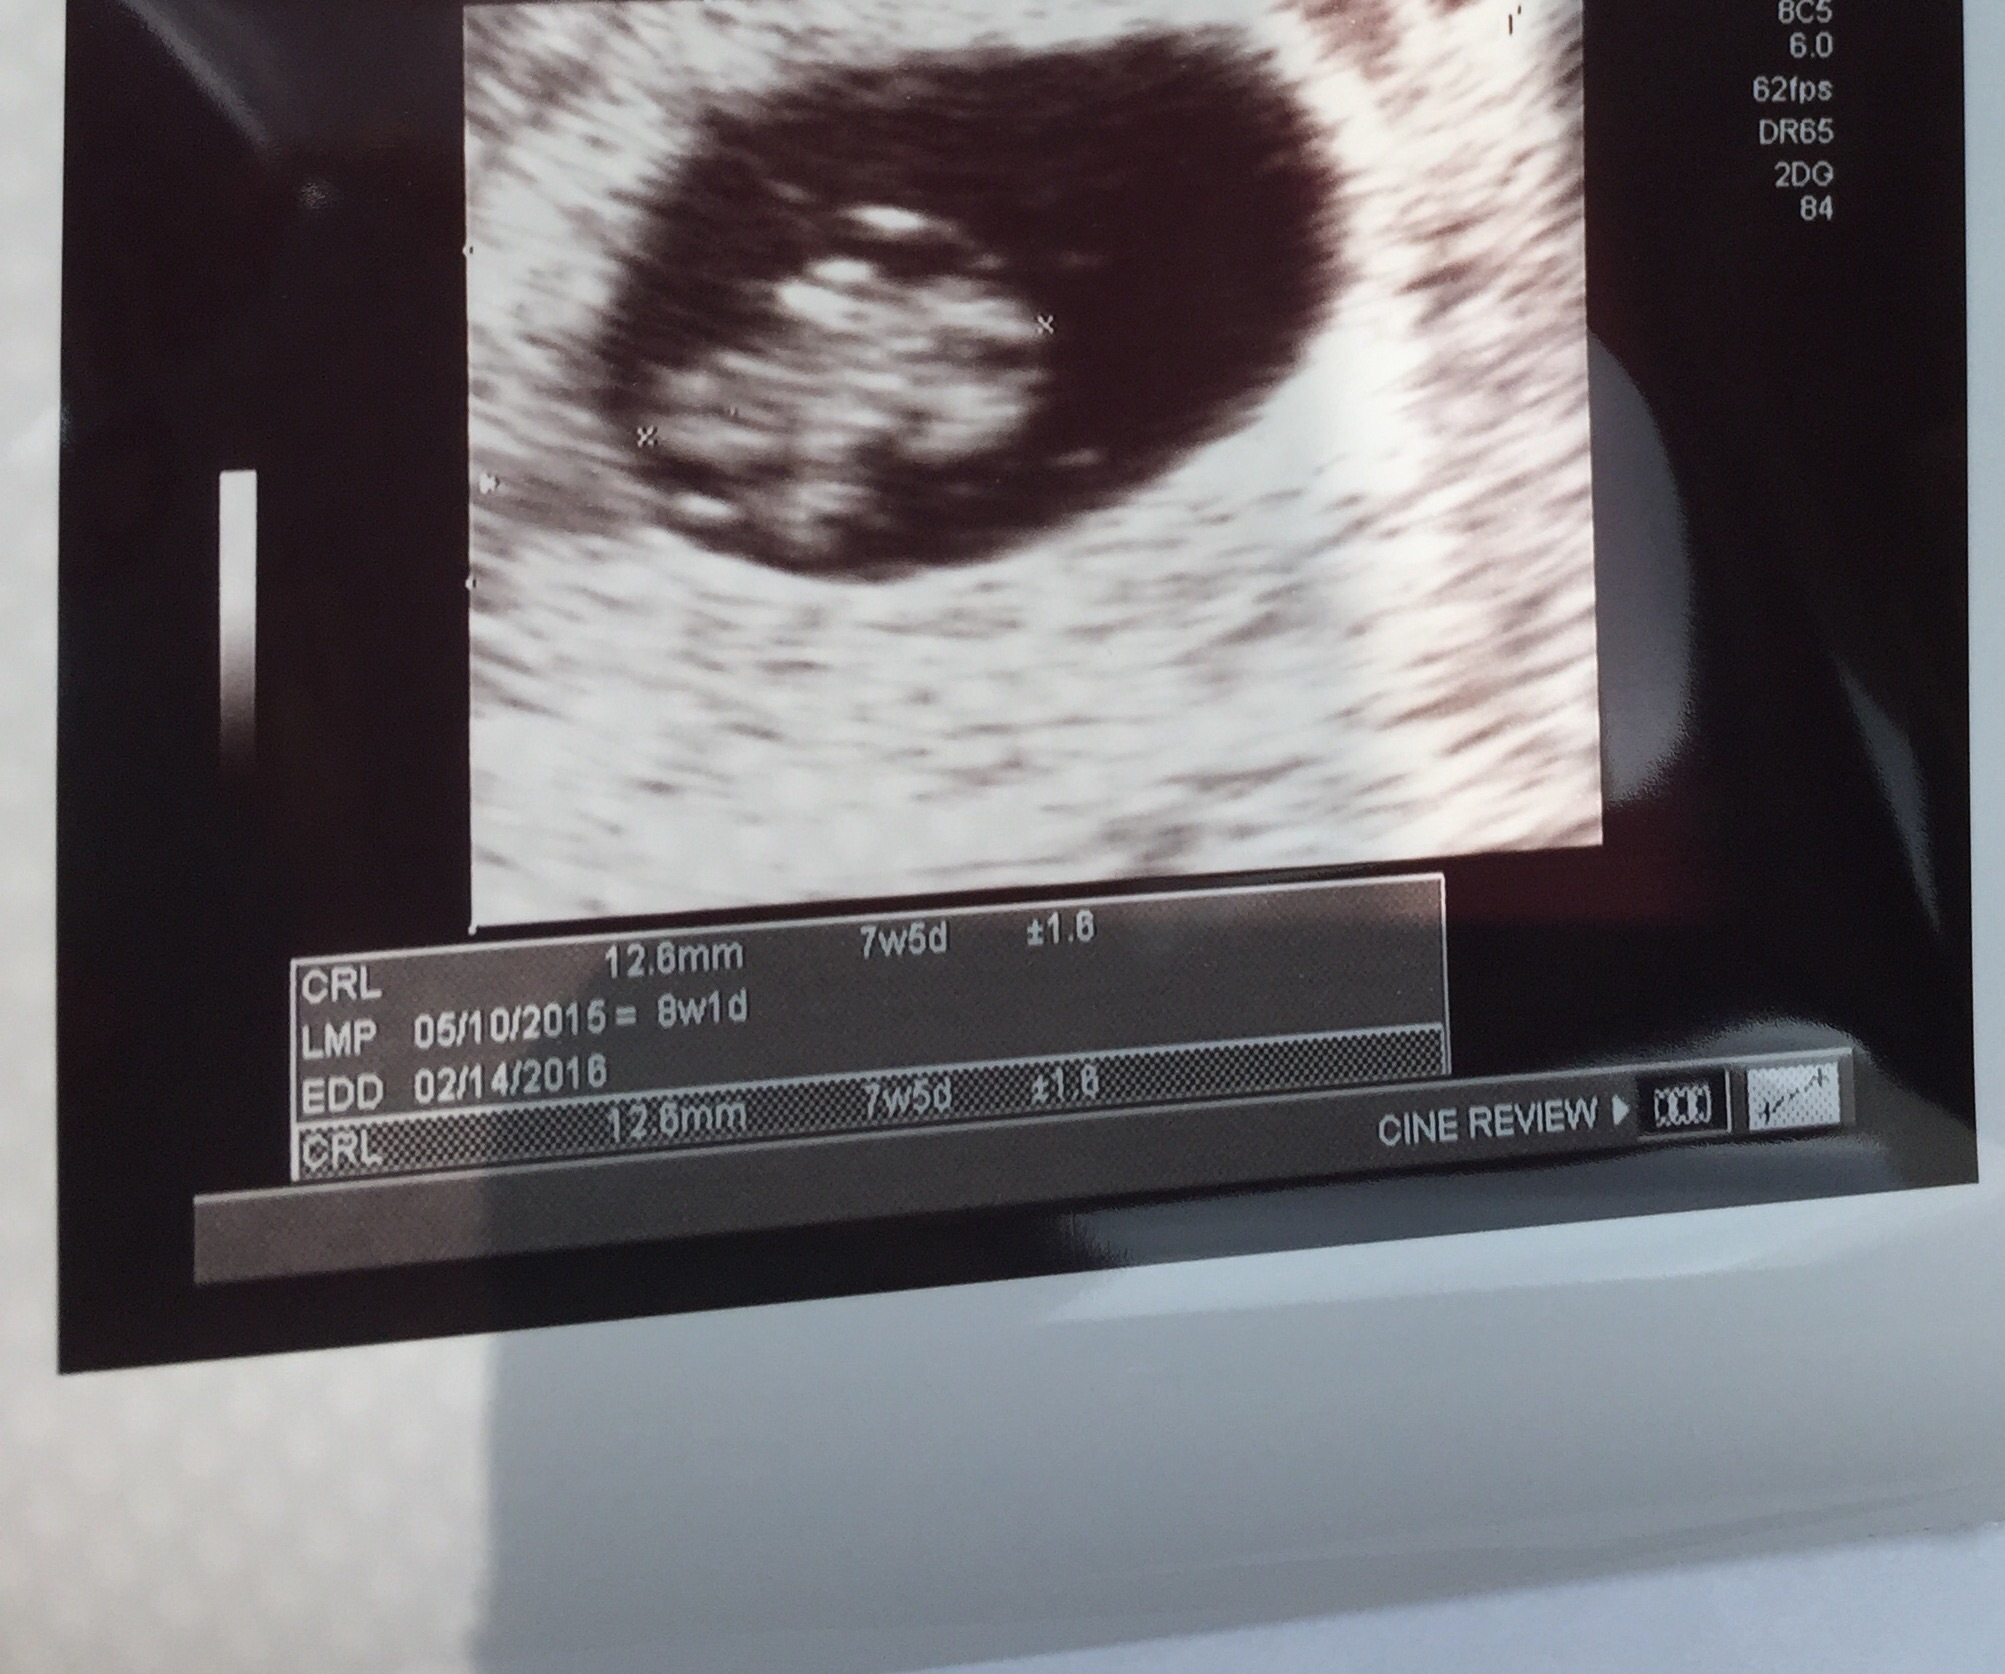

• So glad I get to finally post on this thread! First US today. I was really worries because my progesterone was low, but baby looks good :) heartbeat was 143. Not as far along as we originally thought, but not far behind. Right at 7 weeks. Due 2/23 :)

Finally got to see our peanut.

image